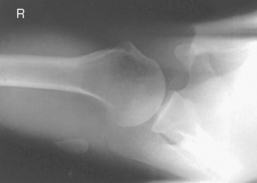

Tangential projection—intertubercular (bicipital) groove (Fisk modification) (S)

Tangential projection intertubercular groove critique